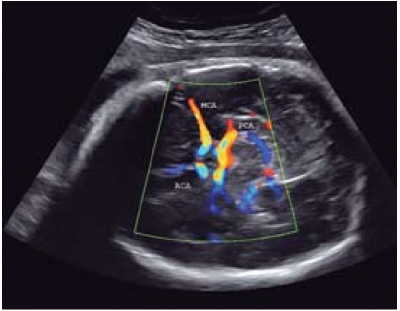

תגובת המרכוז של זרימת הדם הודגמה בתת-חמצון (Hypoxia) עוברי, כאשר הירידה המירבית במדד הפעימתיות הודגמה בעת ירידת הלחץ החלקי של החמצן בין 2 ל-4 סטיות תקן. ברמות גבוהות יותר, מדד הפעימתיות נוטה לעלות, כנראה בגלל התפתחות בצקת מוחית[25]. בהיריונות עם האטת גדילה מודגמת פעימתיות ירודה בכל העורקים התוך גולגולתיים בהשוואה להיריונות תקינים, עדות לתוצא שימור המוח (תמונה 3). עם זאת, למרות התגובה הכוללנית של חלוקה מחדש, יש חילוקי דעות לגבי השימוש במדד הפעימתיות המוחי כאמצעי בלעדי לניבוי האטת גדילה. כמדד בודד, מדד הפעימתיות בעורקי הטבור נשאר המדד היעיל לצורך זה[26].